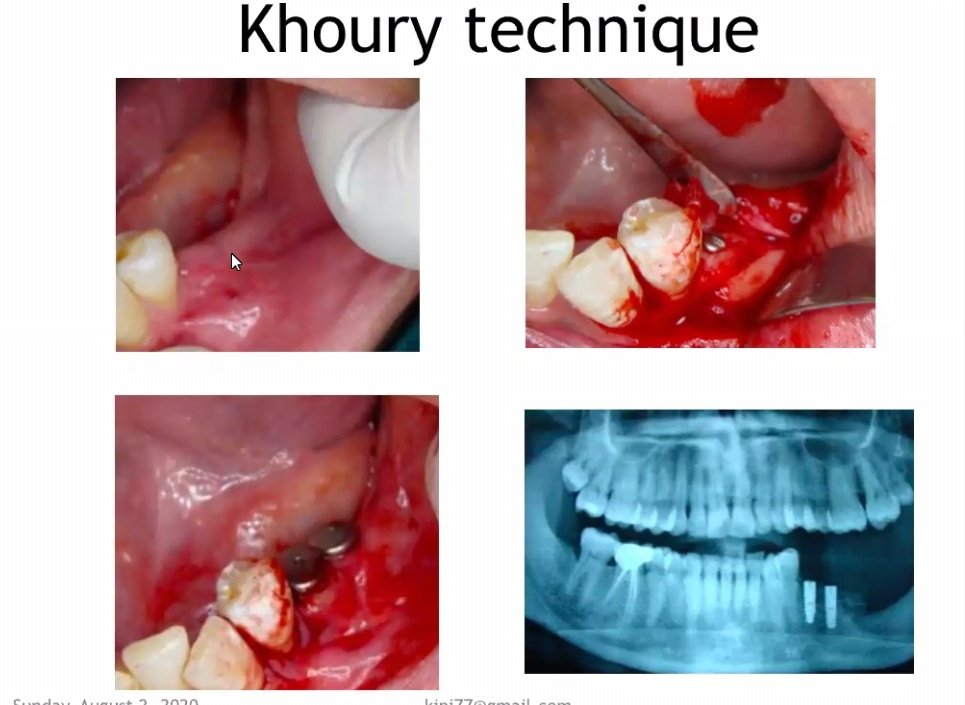

It is also called as split bone block technique / shell technique.